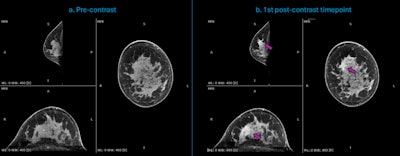

Dedicated breast CT acquisitions of a 44-year-old woman with newly diagnosed invasive ductal carcinoma (IDC) of high aggressiveness (grade 3) in the right breast. (a.) Multiplanar reconstruction of the precontrast acquisition (t = 0 seconds); (b.) Multiplanar reconstruction of the first acquired postcontrast timepoint (t = 90 seconds), indicating the enhancing malignant lesion (purple arrow), in a case with strong background parenchymal enhancement (BPE). Courtesy of Dr. Ritse Mann, NKI, Netherlands Cancer Institute.

The researchers acquired, reconstructed, and registered the images. They performed temporal subtraction by subtracting the precontrast from the registered postcontrast images to highlight the lesion-related signal intensity enhancement.